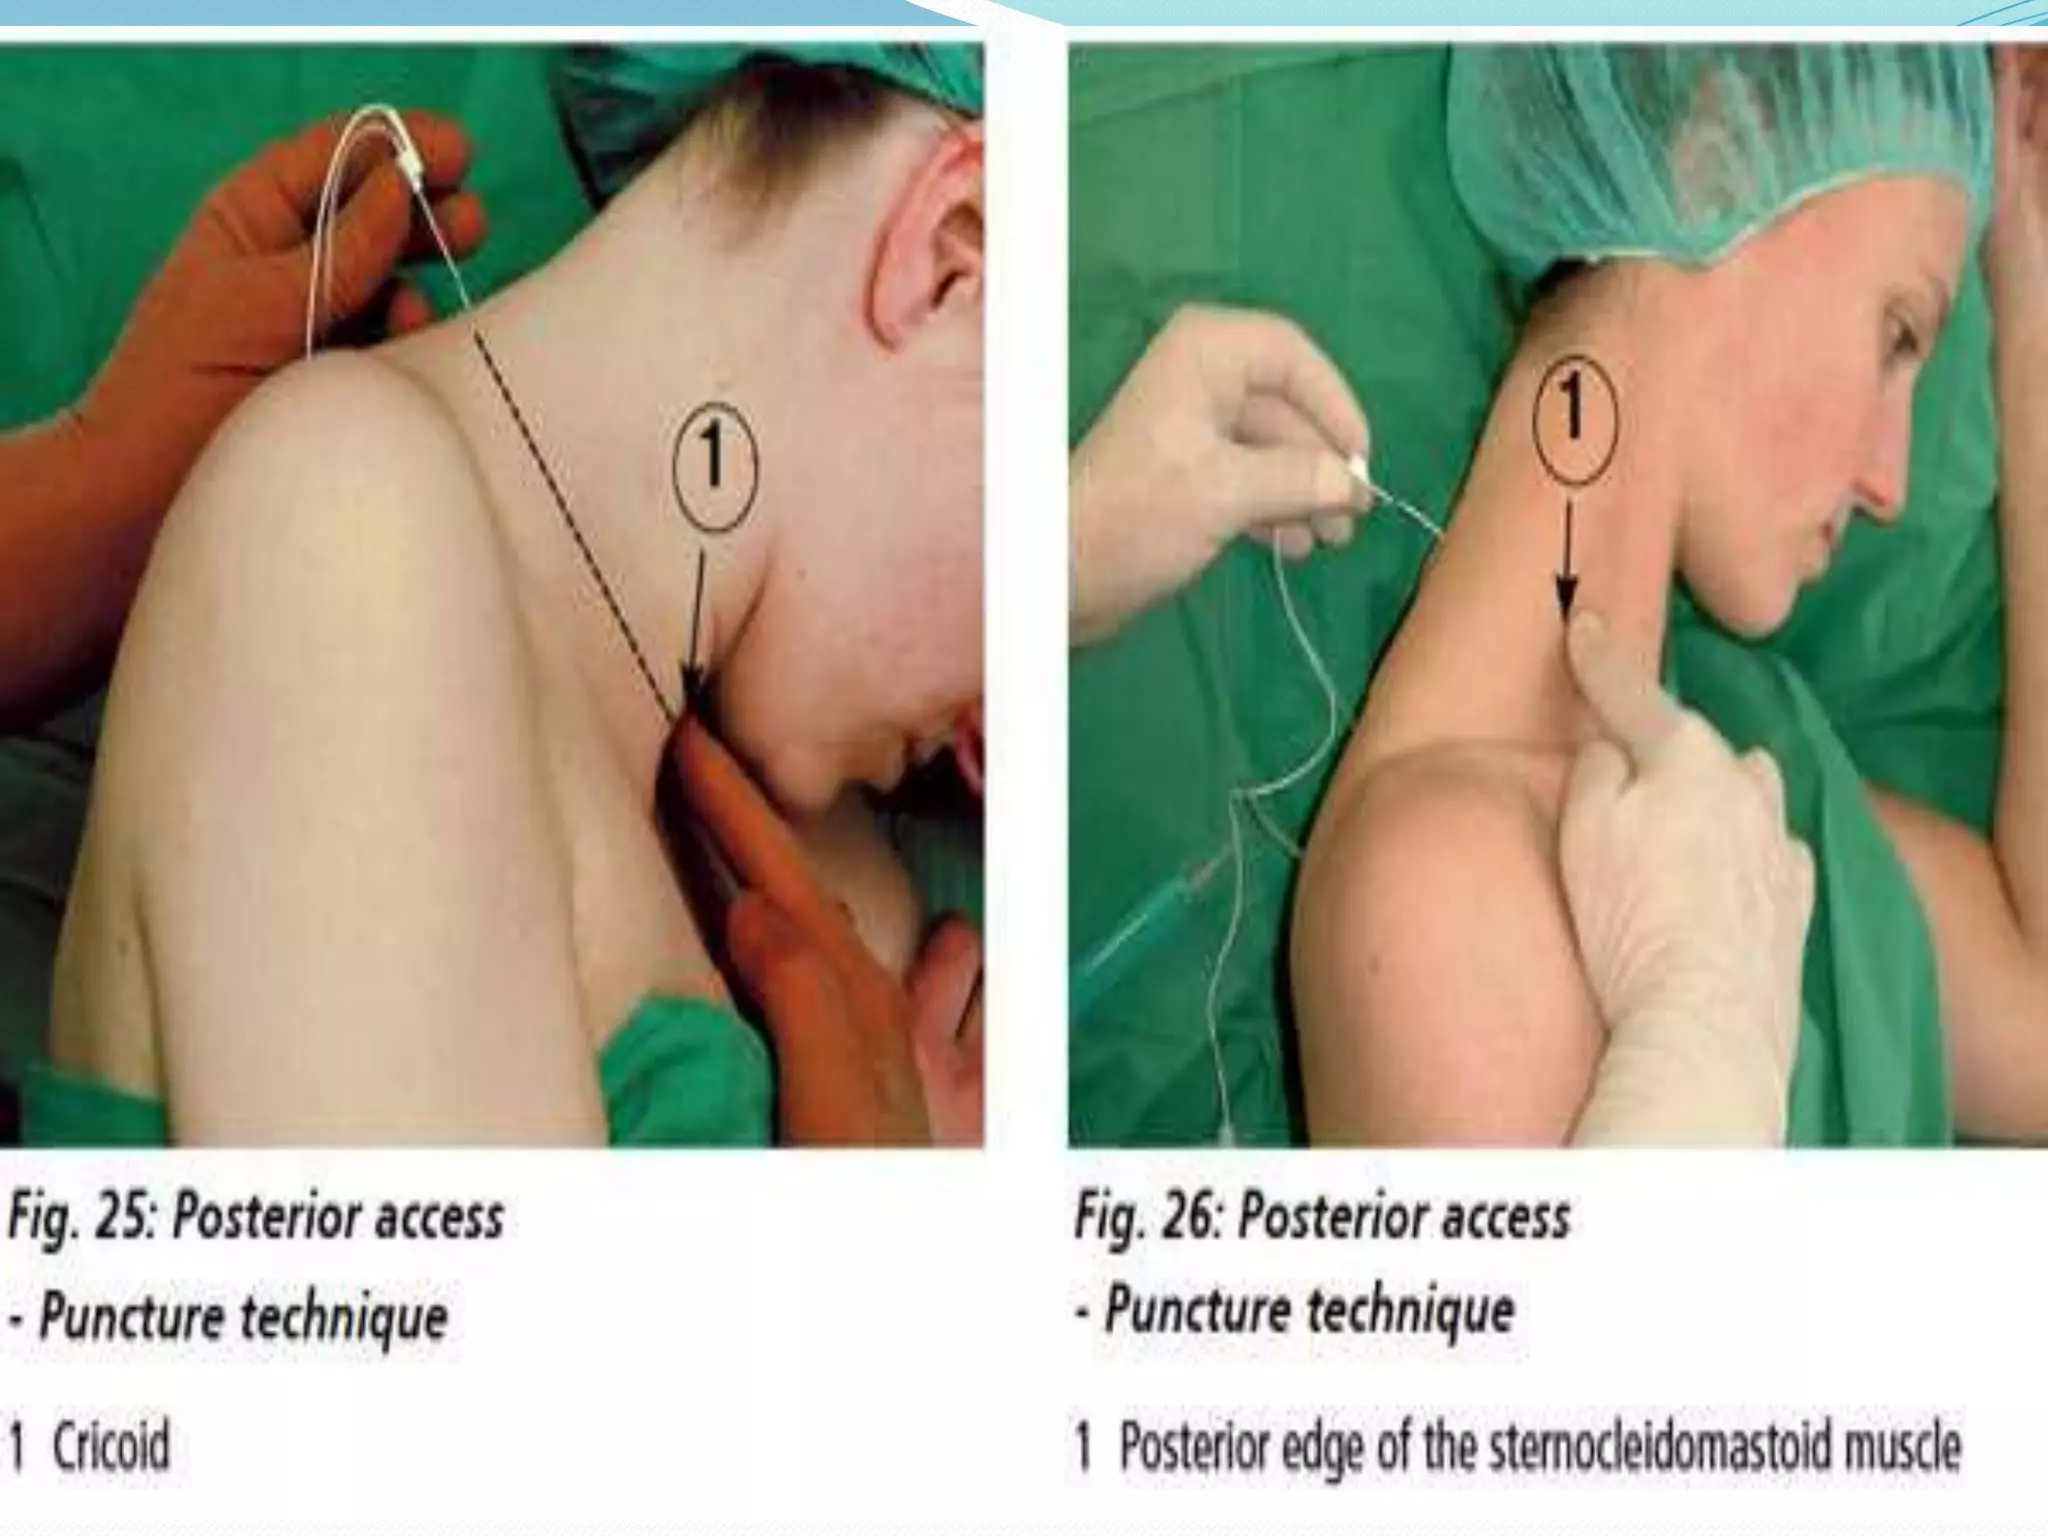

This document provides an overview of brachial plexus anatomy and techniques for brachial plexus nerve blocks. It begins with a description of the brachial plexus formation from cervical and thoracic nerve roots and its branching pattern. Four main approaches for brachial plexus nerve blocks are described: interscalene, supraclavicular, infraclavicular, and axillary. Details are provided on the anatomy and techniques for performing interscalene and supraclavicular brachial plexus blocks. Ultrasound guidance is discussed as an advancement which allows real-time visualization of needle and nerve. Complications are also summarized.